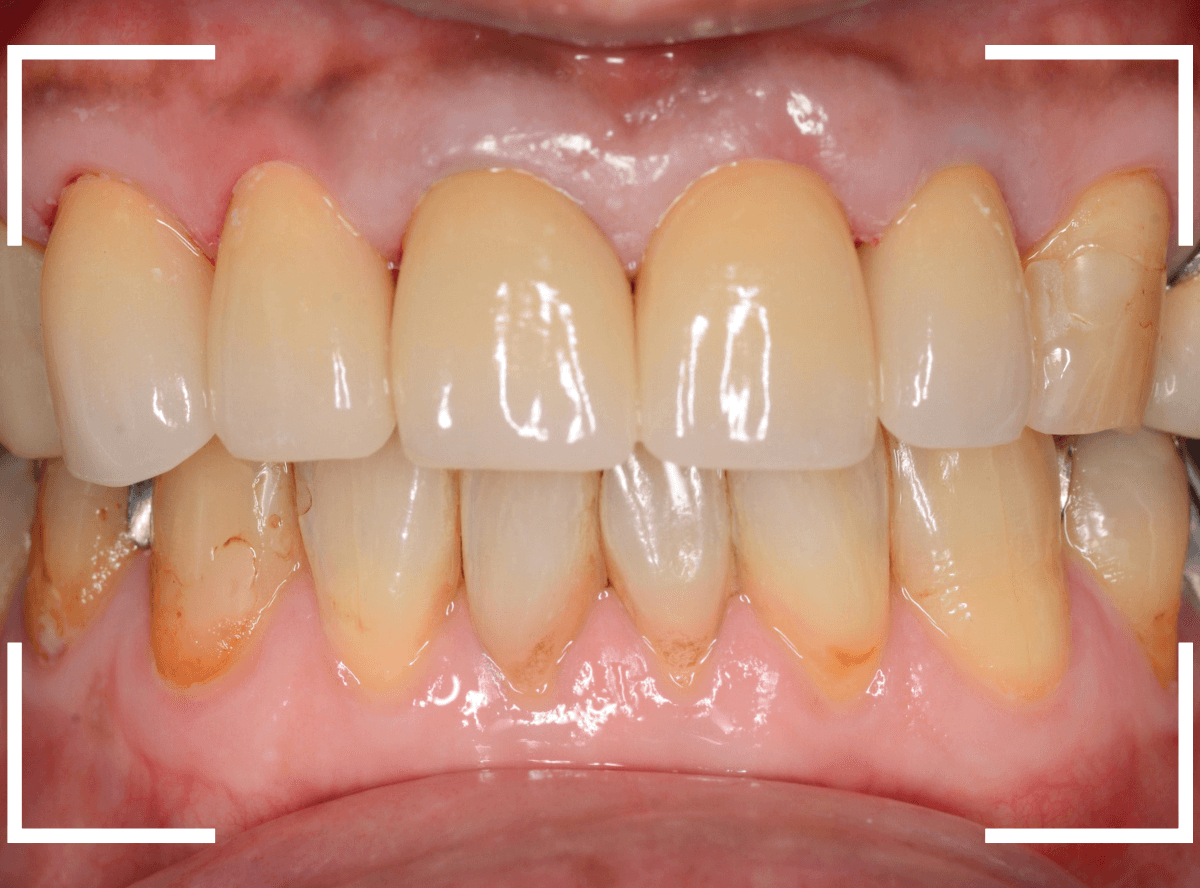

以前に治療した上のさし歯を綺麗にやり直したいというご相談の患者さんです。

保険診療で行うさし歯「レジン前装冠」が入っています。

「レジン前装冠」は裏から撮影した写真を見ていただければわかるように、銀歯の上にレジン(プラスチック)を盛ったさし歯で、実質的には銀歯です。

銀歯の上にプラスチックを盛るために、歯をかなり大きく削る必要があったり、短期間で劣化・変色する(この方の差し歯も劣化してのっぺりした黄土色になっています)、金属の色素が歯肉に溶け出して歯肉が黒くなる(メタル・タトゥー)などのデメリットがあります。

お口の中でsetしたところです。

お口の中に入った状態のビフォーアフターです。

見た目の印象も大きく変わったかと思います。

また、以前のさし歯に比べて、舌触りがとてもよくなったとの感想もいただきました。